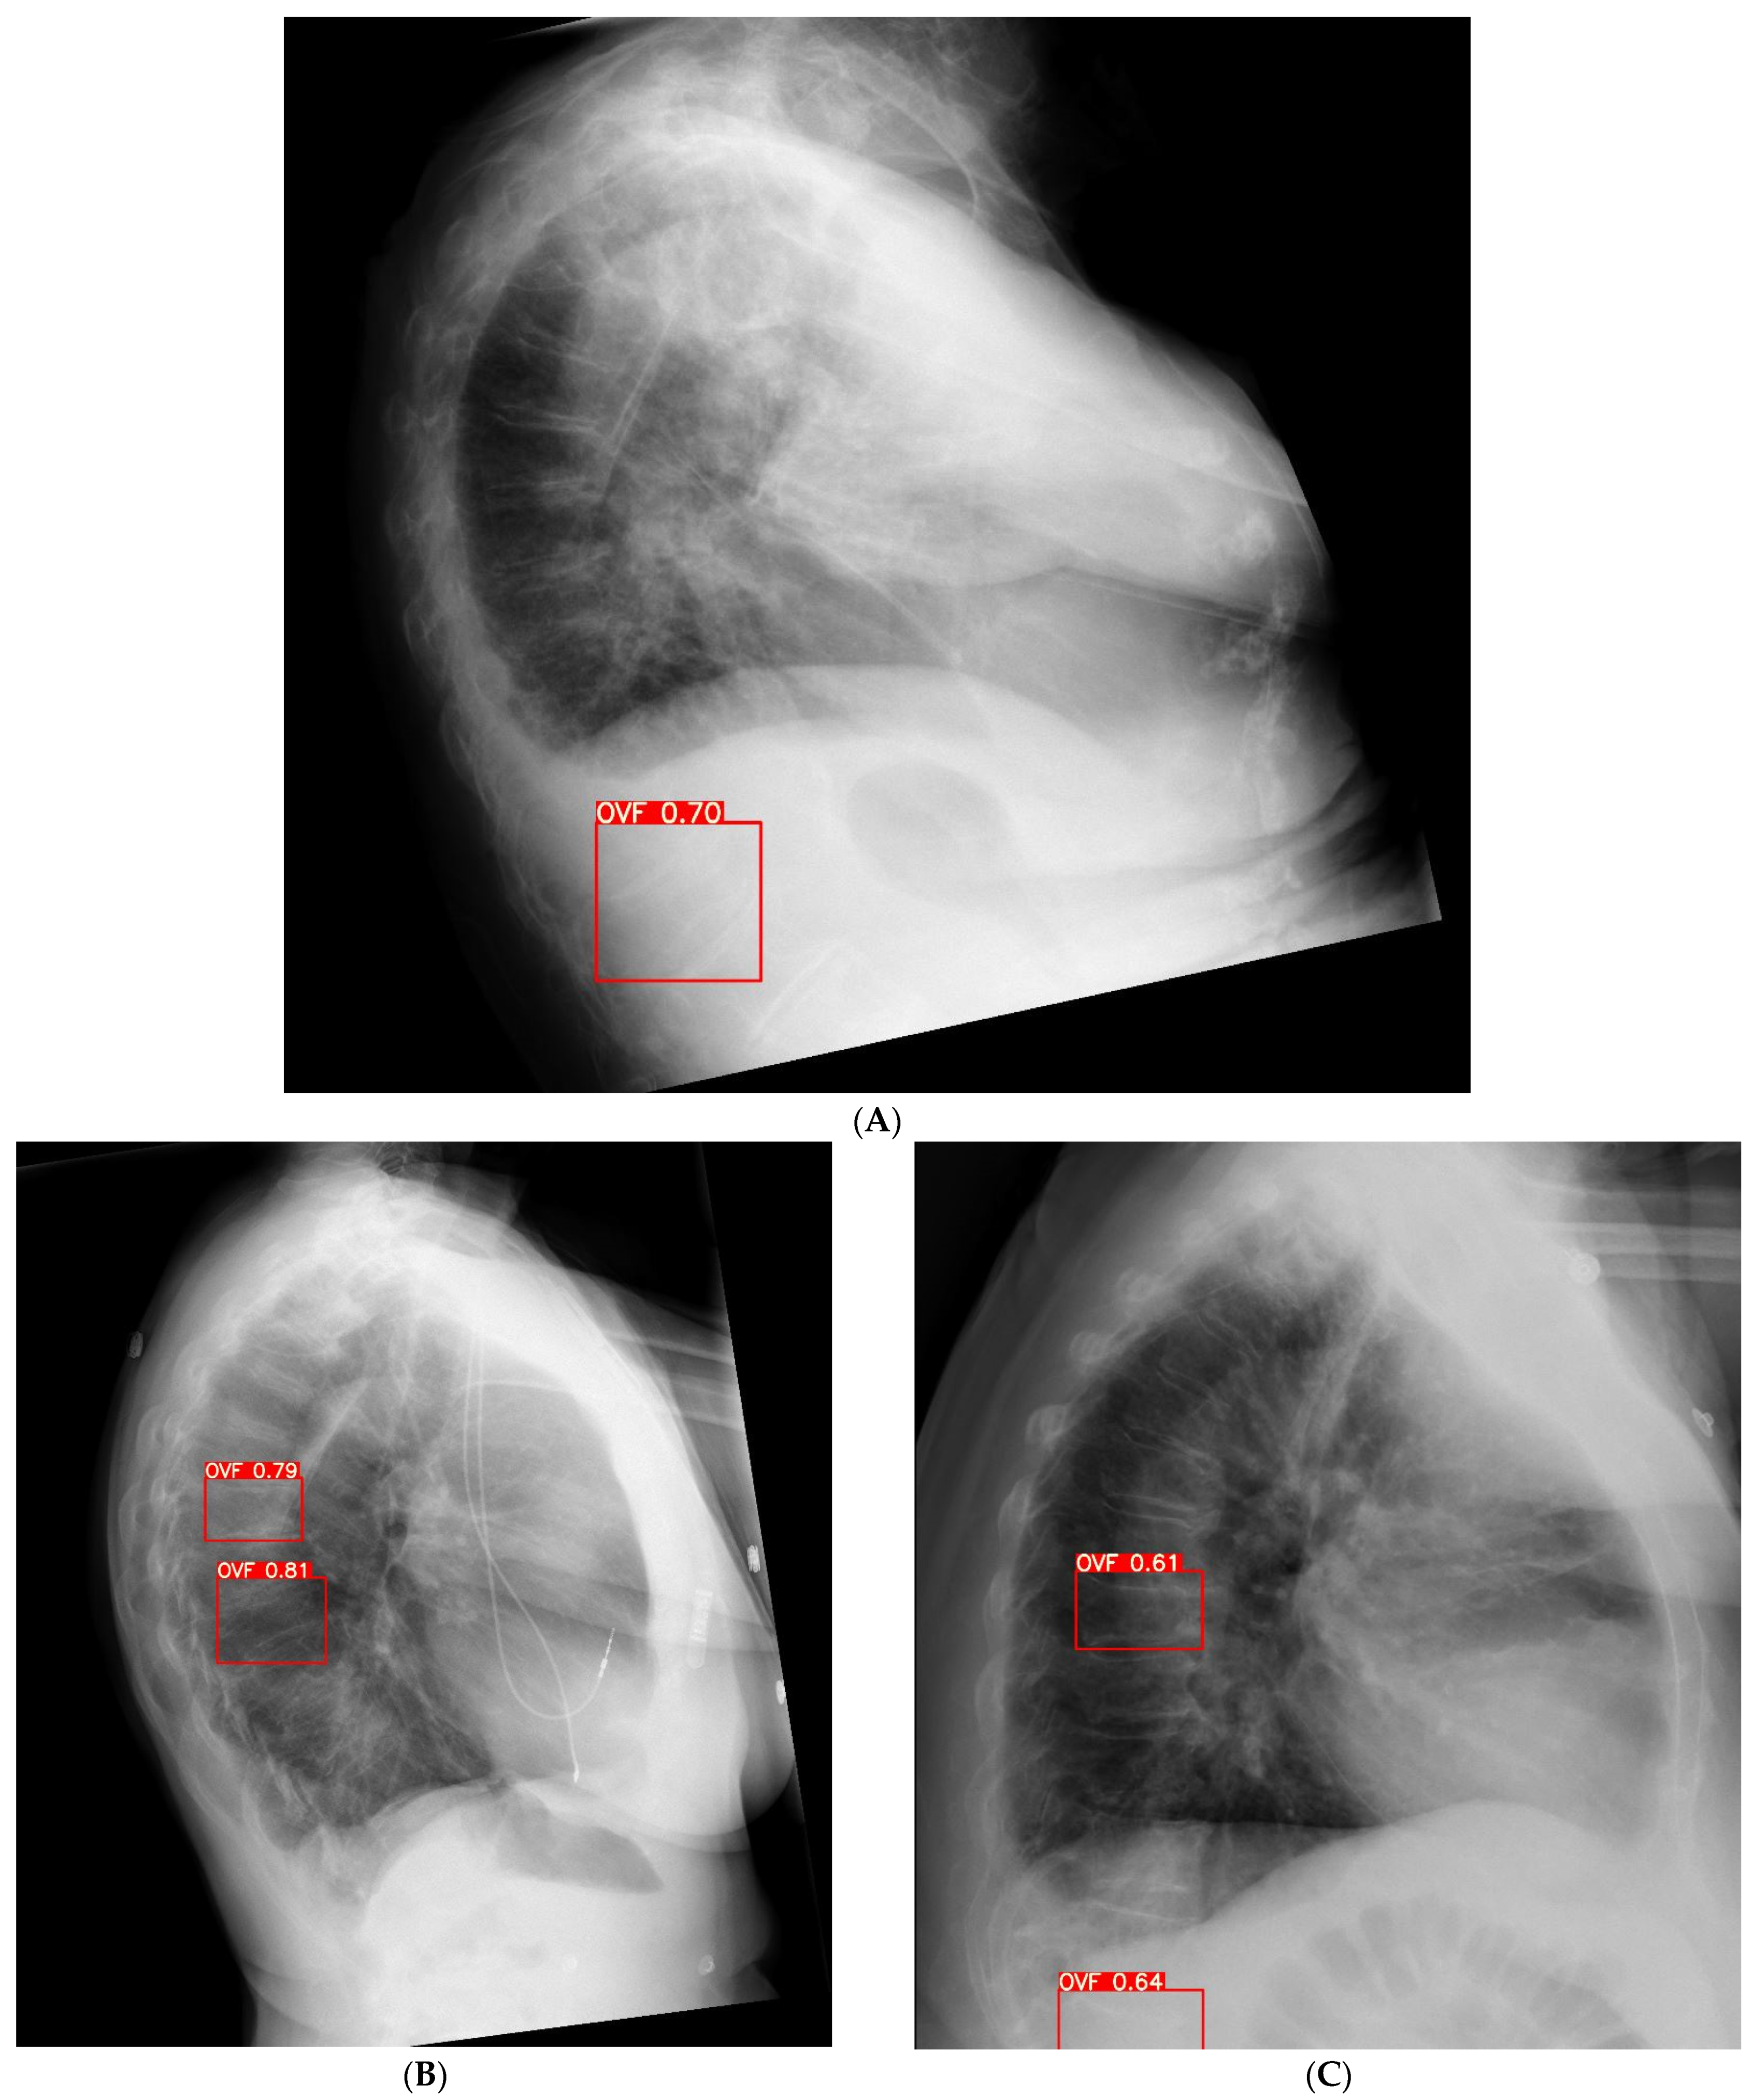

2.2. Image Analysis Using Ofeye 1.0 for Automatic Detection of OVFs

- Xiao, B.H.; Zhu, M.S.; Du, E.Z.; Liu, W.H.; Ma, J.B.; Huang, H.; Gong, J.S.; Diacinti, D.; Zhang, K.; Gao, B.; et al. A software program for automated compressive vertebral fracture detection on elderly women’s lateral chest radiograph: Ofeye 1.0. Quant. Imaging Med. Surg. 2022, 12, 4259–4271. [Google Scholar] [CrossRef]